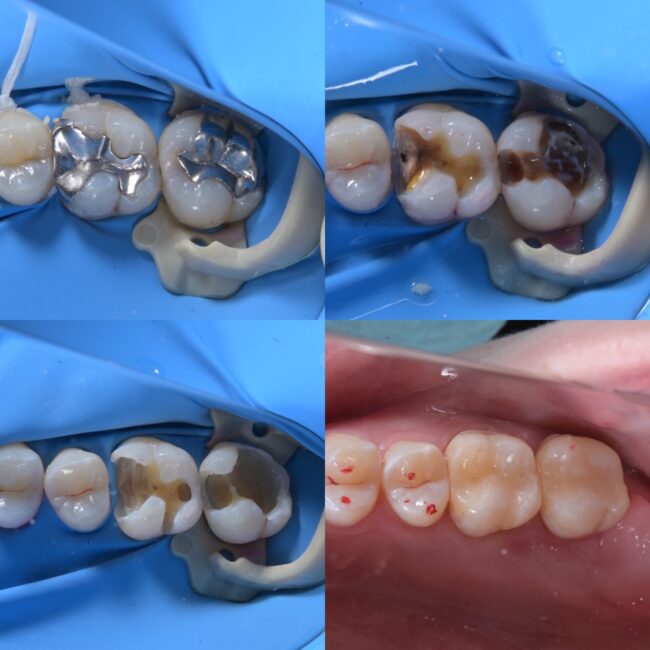

1枚目は実際に治療中の写真になりますが、大変深い虫歯で一部歯の神経が露出しましたが、神経を取ることなく治療することができました。

2枚目はその治療の流れになります。銀歯が接着しておらずその下が大きな虫歯になっており、露髄(歯の神経が露出)したため歯髄保護を行なった上で症状が出ないか確認するため一時的な修復処置まで終わらせた状態になります。